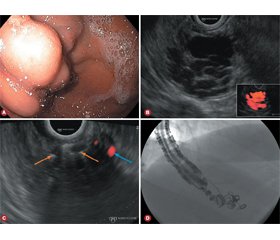

ЕСГ є цінним інструментом для діагностики, планування й оцінки ефективності лікування ШВ, визначення небезпеки повторної кровотечі, а також допомагає візуалізувати варикозне розширення вен, перфорантні і колатеральні вени та дозволяє прогнозувати варикси високого ризику. Під час стандартної ендоскопії верхніх відділів наявність ШВ часто складно визначити, особливо при активній кровотечі [3]. Крім того, не завжди легко оцінити розмір та наявність живлячих судин. Це особливо важливо, оскільки фактори ризику повторної кровотечі зі ШВ включають розмір варикозного розширення і наявність парашлункових вен [4]. Із цієї причини EСГ може мати переваги в лікуванні ШВ, оскільки вона може краще візуалізувати стінку шлунка та пов’язану з нею судинну мережу, навіть в умовах активної кровотечі [5] (рис. 1). Перевагою EСГ перед стандартною ендоскопією також є можливість негайної післялікувальної допплерівської оцінки варикозного ложа та його аферентних притоків, щоб забезпечити повну облітерацію [6, 7].

Останнім часом досягнення в ендоваскулярній терапії під контролем EСГ дозволили впроваджувати нові втручання [8]. Хоча EСГ може бути корисною як діагностичний допоміжний засіб, її терапевтичний потенціал набув більшого визнання останнім часом. Під контролем EСГ різні гемостатичні адгезиви та пристрої можуть бути введені в ШВ, включаючи ціаноакрилат (EСГ-ЦA) (рис. 2), спіралі (EСГ-СП), спіралі і ЦA (EУСГ-СП/ЦА), тромбін (EСГ-ТР) і спіралі з желатиновою губкою, що розсмоктується (EУСГ-СП/РЖГ) [9].